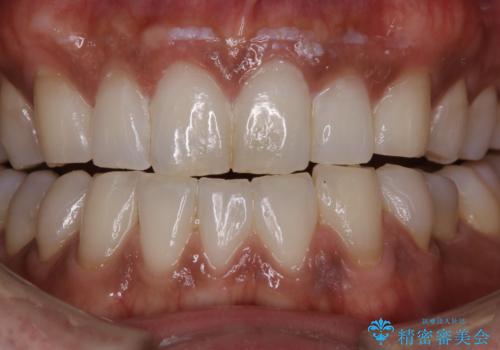

前歯の着色をPMTCできれいに

担当医 歯科衛生士